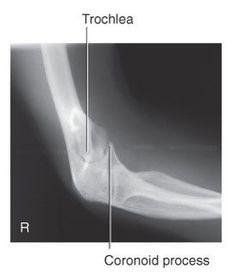

A. radial and coronoid fossas B. capitulum C. trochlea D. coronoid process E. radial tuberosity F. radial neck G. radial head H. trochlear sulcus I. trochlear notch J. olecranon process K. epicondyle L. olecranon fossa

G. superimposed epicondyles of humerus I. trochlear sulcus J. trochlear notch K. outer ridges of capitulum and trochlea L. coronoid process of ulna M. radial head N. radial neck